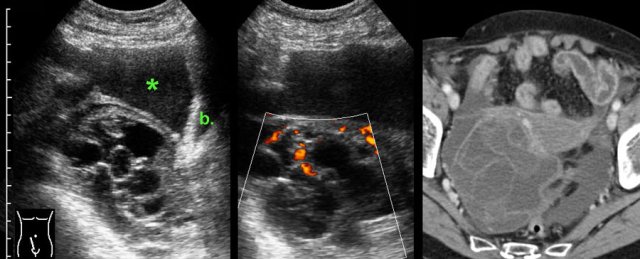

TOA case 1

Young,

very ill woman with acute LLQ pain and a CRP of 260. Left of the uterus a massively

enlarged (6 x 7 x 8 cm) ovary is found.

The individual follicles are enlarged, ill-defined

and filled with turbid fluid (pus).

Note the hyperechoic halo around this inflamed

mass.

Since

there is no apparent involvement of the Fallopian tube, strictly speaking this

is an oophoritis.

Nevertheless, usually the term of tubo-ovarian abscess is used.